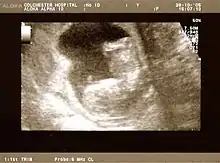

Fetus at 20 weeks

Obstetric ultrasonography is routinely used for dating the gestational age of a pregnancy from the size of the fetus, determine the number of fetuses and placentae, evaluate for an ectopic pregnancy and first trimester bleeding, the most accurate dating being in first trimester before the growth of the foetus has been significantly influenced by other factors.[22] Ultrasound is also used for detecting congenital anomalies (or other foetal anomalies) and determining the biophysical profiles (BPP), which are generally easier to detect in the second trimester when the foetal structures are larger and more developed.[23]

X-rays and computerized tomography (CT) are not used, especially in the first trimester, due to the ionizing radiation, which has teratogenic effects on the foetus.[24] No effects of magnetic resonance imaging (MRI) on the foetus have been demonstrated,[25] but this technique is too expensive for routine observation. Instead, obstetric ultrasonography is the imaging method of choice in the first trimester and throughout the pregnancy, because it emits no radiation, is portable, and allows for realtime imaging.[26]

The safety of frequent ultrasound scanning has not been confirmed. Despite this, increasing numbers of women are choosing to have additional scans for no medical purpose, such as gender scans, 3D and 4D scans.[27] A normal gestation would reveal a gestational sac, yolk sac, and fetal pole.[28]

The gestational age can be assessed by evaluating the mean gestational sac diameter (MGD) before week 6, and the crown-rump length after week 6. Multiple gestation is evaluated by the number of placentae and amniotic sacs present.[29]